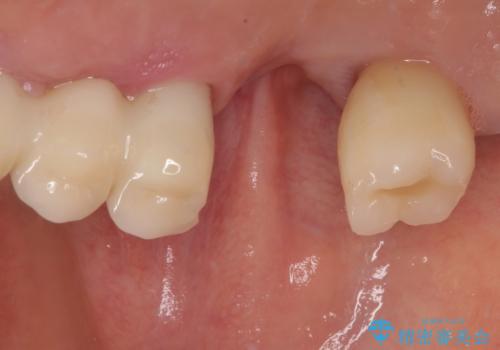

インプラントの初期固定も埋入後の生着もスムーズであったので、埋入から3ヶ月で無事に治療を終えることができました。